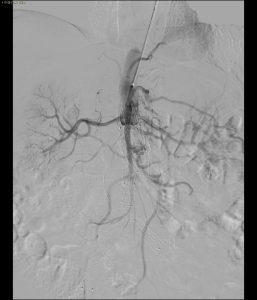

Il paziente si è presentato alla nostra osservazione con una storia clinica di EVAR (effettuata circa un anno prima con endoprotesi aortica Cook). Gli esami di controllo mediante angio-TC hanno rivelato una complicanza severa: la trombosi completa dell’innesto al di sotto delle arterie renali.

- Analisi del caso: Trombosi completa endograft

- Ricanalizzazione con filo guida

- Predilatazione

- Stenting